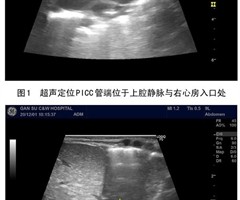

超声引导下在新生儿不同部位留置PICC的应用效果研究

摘要:目的:探讨超声引导下分别在新生儿上肢静脉和下肢静脉留置 PICC 的临床效果差异。方法:选取我院收住630例住院患儿为研究对象,随机分为上肢静脉组和下肢静脉组,记录并分析两组患儿的置管耗时、出血量及一次穿刺成功率等指标。结果:下肢静脉...